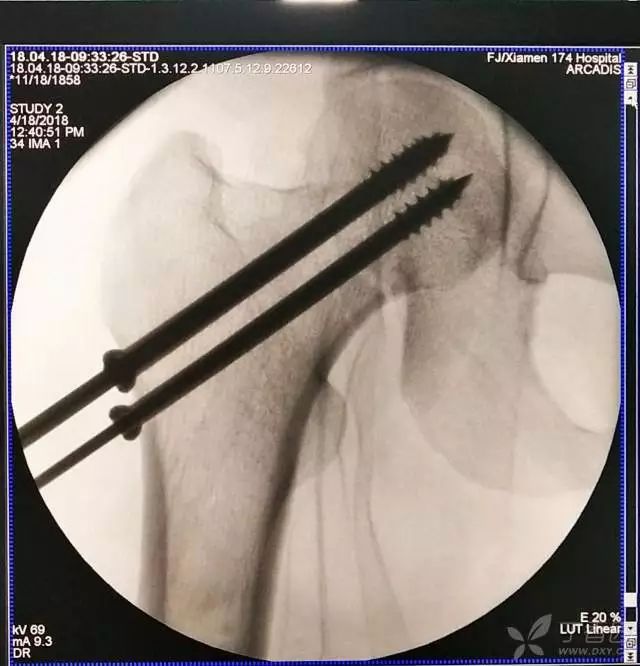

5. 打入第一枚倒品字下方导针,跟体外导针基本重叠

6. 然后依次打入倒品字上方的两枚导针

打入第一枚导针时应非常小心,一定是要和体外的导针保持方向一致。还有一个小细节是,进针前笔者一定会体外先摸股骨大粗隆的外侧,判断前后位置,进第一枚导针到达股骨外侧后,用针尖在股骨外侧面前后滑动,再次判断进针点是否居中。

第一枚导针一定要打好,进针一半时透视看看方向,如果不好,及时调整。笔者做股骨颈骨折有个体会,尽量一次性进针成功,反复穿针很容易导针滑入原道,既影响复位维持,也会使再次穿针愈加困难。

第一枚导针打好以后,根据该导针距离股骨颈下方的距离(如下图),确定上方两枚导针的距离,距离过近,会导致螺钉打架或者汇聚,过远则打不到股骨颈内。

打第 2、3 枚导针有个小技巧,首先用导向器套住第一枚导针判断合适的距离,以及上方两枚导针之间的距离,此时顺着导向器插入第 2 枚导针。

这里需要注意的是,不是沿着导向器直接打进去(这样往往打入的导针无法与第一枚导针平行,不好看),笔者会稍打进去一点能把针固定住就好,然后把导向器退出来,看体外针尾平行方向往里打。这样确实打出来的导针都比较平行。最后把第三枚导针按第二枚的步骤打进去就可以了。